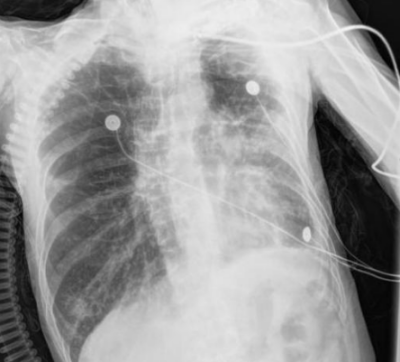

呼吸与危重症医学科救治。该科副主任朱锦琪、梁伟军及团队高度警觉免疫治疗病史可能带来的并发症,详细追溯他两年的免疫治疗用药记录,对其近期肺部CT影像进行反复对比和深入研判,认为其符合免疫检查点抑制剂相关肺炎(CIP)的典型表现,确诊其为迟发性、重度(4级)免疫检查点抑制剂相关肺炎。

免疫检查点抑制剂相关肺炎4级